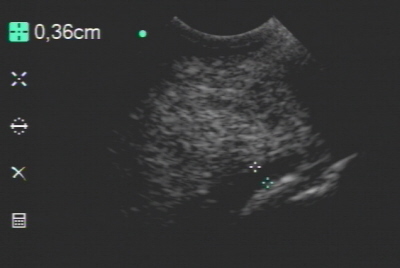

Tiefe Beugesehne im Ultraschall unauffällig